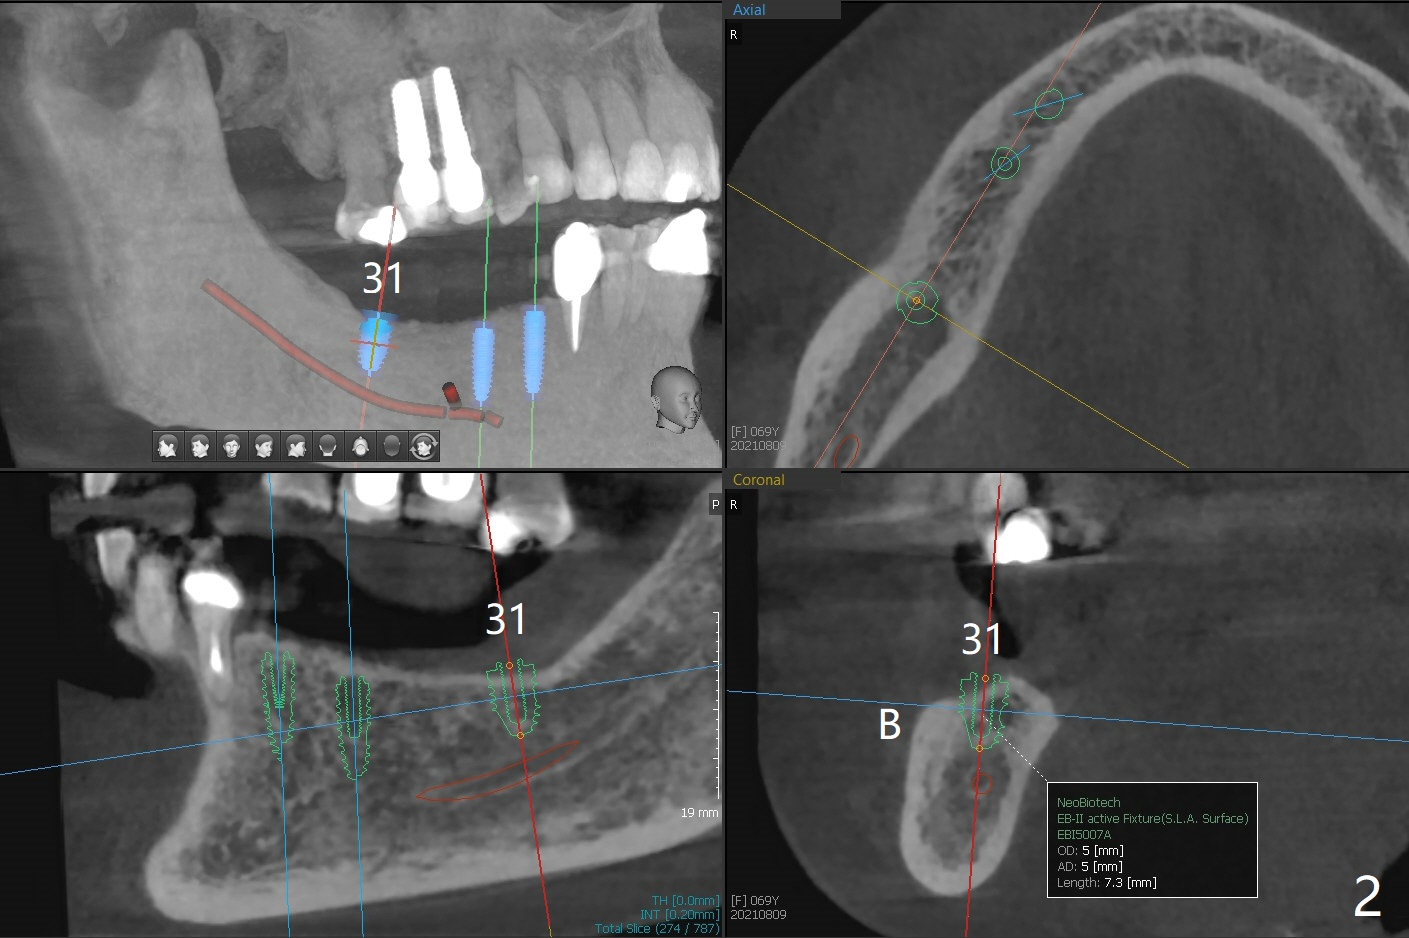

A 69-year-old woman requests conversion of the lower RPD to implant restoration. Initially implants are going to be placed at #19, 28, 29, and 31 (Fig.1,2). CT exam shows short bone at #31 (Fig.2). Please try to place implants at #28-30 for a cantilever FPD (Fig.3) if reasonable. When making guide(s), please use #18 residual roots as a distal stopper (Fig.1) if practical.